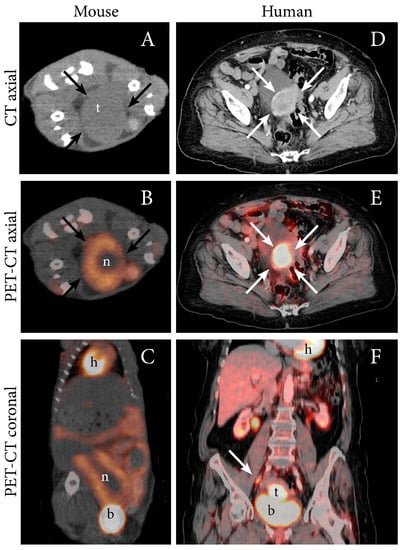

| MRI T1, T1+C, T2, DW, ADC | Present preclinical imaging findings using multiple imaging techniques | Tumor can be delineated using anatomic sequences and exhibits restricted diffusion with low ADC-values | Ishikawa cells, orthotopic, NSG mice | [12] |

| PET FDG | Present preclinical imaging findings using multiple techniques | Growth of primary tumor and metastases can be detected Total lesion glycolysis was calculated (SUVmean x MTV) | Ishikawa cells and PDX-model, orthotopic, NSG mice | [12] |